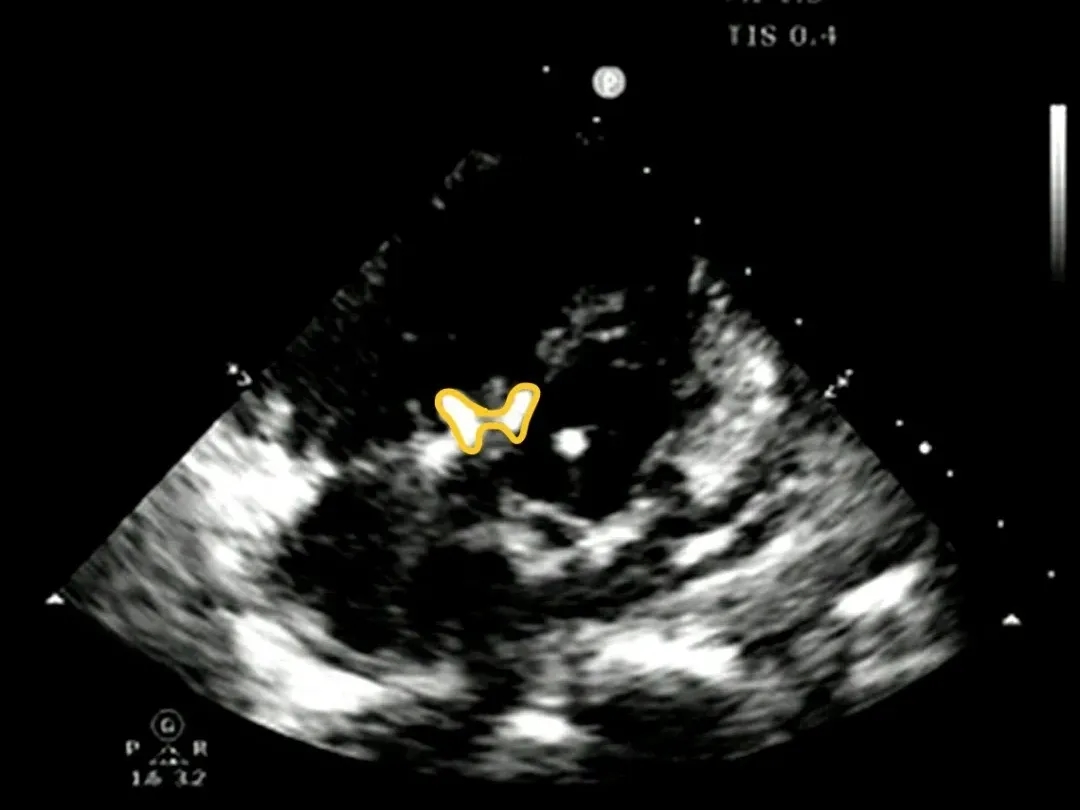

锁定后牵拉及释放

牵拉试验,封堵器稳定无移位,释放封堵器后超声下确认无残余分流,无主动脉瓣反流,三尖瓣反流同术前无增加。

大动脉短轴切面,封堵器释放后双盘紧贴间隔,呈现完美“工字形蝴蝶形”,顺应VSD形态及瓣膜形态。

MemoSorb全降解VSD封堵器展现了极佳的顺应性,在通过长隧道、小出口的VSD后,能顺利从“长哑铃”形态展开并固定为贴壁良好的“蝴蝶”形态。术后即刻超声评估显示,伞盘封堵完全,对相邻瓣膜无任何影响,主动脉瓣及三尖瓣均未出现反流。

两次随访中,MemoSorb全降解封堵器形态稳定、无位移、无残余分流、无主动脉瓣反流,三尖瓣反流与术前无明显差异。

1.可降解VSD封堵器的最大优势为顺应性强,可自如顺应长隧道小出口型VSD形态,“长哑铃形态”锁定成型后成为“蝴蝶形态”,伞盘紧贴间隔,彩色血流主动脉瓣无反流,三尖瓣反流无增加,瓣膜启闭丝毫无影响。

2.封堵过程中,左盘成型紧贴住左室侧入口,右盘被拉出瘤体,锁定后右盘顺利成型,卡住右室侧上方稍大分流口,封堵器从“长哑铃形”变化成“蝴蝶形”,左盘贴紧左室侧后完全阻挡多出口分流。全降解封堵器的自适应性使其能够被拉长形变,适应曲折长隧道结构,同时成型锁定设计也能够使盘面稳定成盘状形态,卡住分流口。